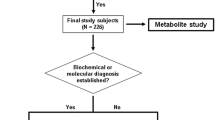

Metabolomic profiling is an emerging technology in the clinical setting with immediate diagnostic potential for the population of patients with Inborn Errors of Metabolism. We present the metabolomics profile of two ABAT deficiency patients both pre- and posttreatment with flumazenil. ABAT deficiency, also known as GABA-transaminase deficiency, is caused by recessive mutations in the gene ABAT and leads to encephalopathy of variable severity with hypersomnolence, hypotonia, hypomyelination, and seizures. Through metabolomics screening of multiple patient tissues, we identify 2-pyrrolidinone as a biomarker for GABA that is informative in plasma, urine, and CSF. These data will enable noninvasive diagnostic testing for the population of patients with disorders of GABA metabolism.

Diagnosis of ABAT deficiency typically relies on a combination of clinical and diagnostic testing including molecular genetic and biochemical testing as well as neuroimaging. Relatively few patients and consequently few pathogenic alleles have been reported for this rare disorder, as a result a definitive diagnosis often relies on other modalities. As with other IEMs, gold standard for diagnosis is assessment of relevant metabolite levels, in this case GABA, which in current practice is most often measured through biochemical testing in the cerebral spinal fluid (CSF) or proton magnetic resonance spectroscopy (MRS) of the brain. However, GABA is typically not included on diagnostic neurotransmitter panels measured in CSF and may not be screened for in MRS unless specified by ordering physician.

Clinical Description

Two patients previously published representing the spectrum of mild and severe ABAT deficiency patients were studied for metabolomics profile. Subject 1 presented in infancy with a severe encephalopathy including intractable seizures, hypotonia, and lethargy (Besse et al. 2015). Brain MRI showed extensive symmetric signal abnormalities in several regions including posterior limbs of the internal capsule, cerebral peduncles, dorsal tegmentum and pons, medulla, and dentate nuclei indicating significant hypomyelination and brain atrophy. This child never achieved any developmental milestones and remains alive in a static state at age 9. This child is one of three similarly affected siblings all of whom were demonstrated to be homozygous for ABAT NM_000663.4 c.631C>T; NP_000654.2 p.Leu211Phe (Besse et al. 2015, 2016).

Subject 2 presented to clinic at 6 months with global developmental delay, hypersomnolence, hypotonia, bilateral opthalmoplegia, and mild choreiform movements without apparent epilepsy (Besse et al. 2016). Oculomotor apraxia was appreciated by age 18 months and cranial MRI conducted showed extensive signal abnormalities in the deep white matter indicative of diffuse, mild hypomyelination. In contrast to Subject 1, no brain atrophy was apparent on MRI. Genetics studies showed this child was compound heterozygous for ABAT NM_000663.4 c.454C>T;p.Pro152Ser and c.1393G>C;p.Gly465Arg.

Metabolic Testing

For both subjects prior to molecular genetic studies, CSF was tested for a panel of neurotransmitters that was reported normal; however, GABA was not included in this panel testing. After molecular studies pointed to ABAT as the pathogenic gene, Subject 1 was tested by proton NMR spectroscopy which showed elevated GABA in the brain (Besse et al. 2015). Subject 2 exome studies identified compound heterozygous mutations in ABAT that were reported as variants of uncertain significance (VUS). Subsequent studies of cerebral spinal fluid (CSF) in this patient demonstrated free GABA level of 247 nmol/L (17–67) and total GABA level of 33.4 μmol/L (4.2–13.4).

Additional metabolic testing on these patients showed no other abnormalities. Subject 1 had normal metabolic testing results for: Krabbe disease, hexosaminidase A and B, CSF protein, glycine, CSF lactate and plasma lactate, urine organic acids, plasma amino acids, very long-chain fatty acids, acylcarnitine profile, urine purines, and urine oligosaccharides. Subject 2 exhibited normal plasma and CSF amino acids.